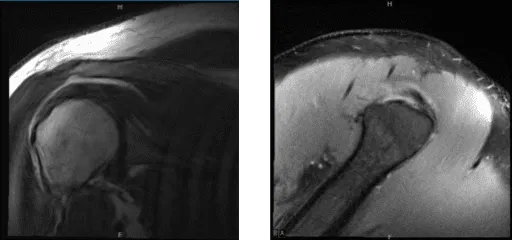

MRI showed an impression as follows: High-grade partial-thickness articular sided tear of the infraspinatus tendon. Moderate supraspinatus tendinosis. Mild long head biceps tendinosis. Mild AC arthrosis. Moderate degenerative tearing of the superior labrum. We discussed treatment options and the patient opted for surgical management.

MRI of right shoulder